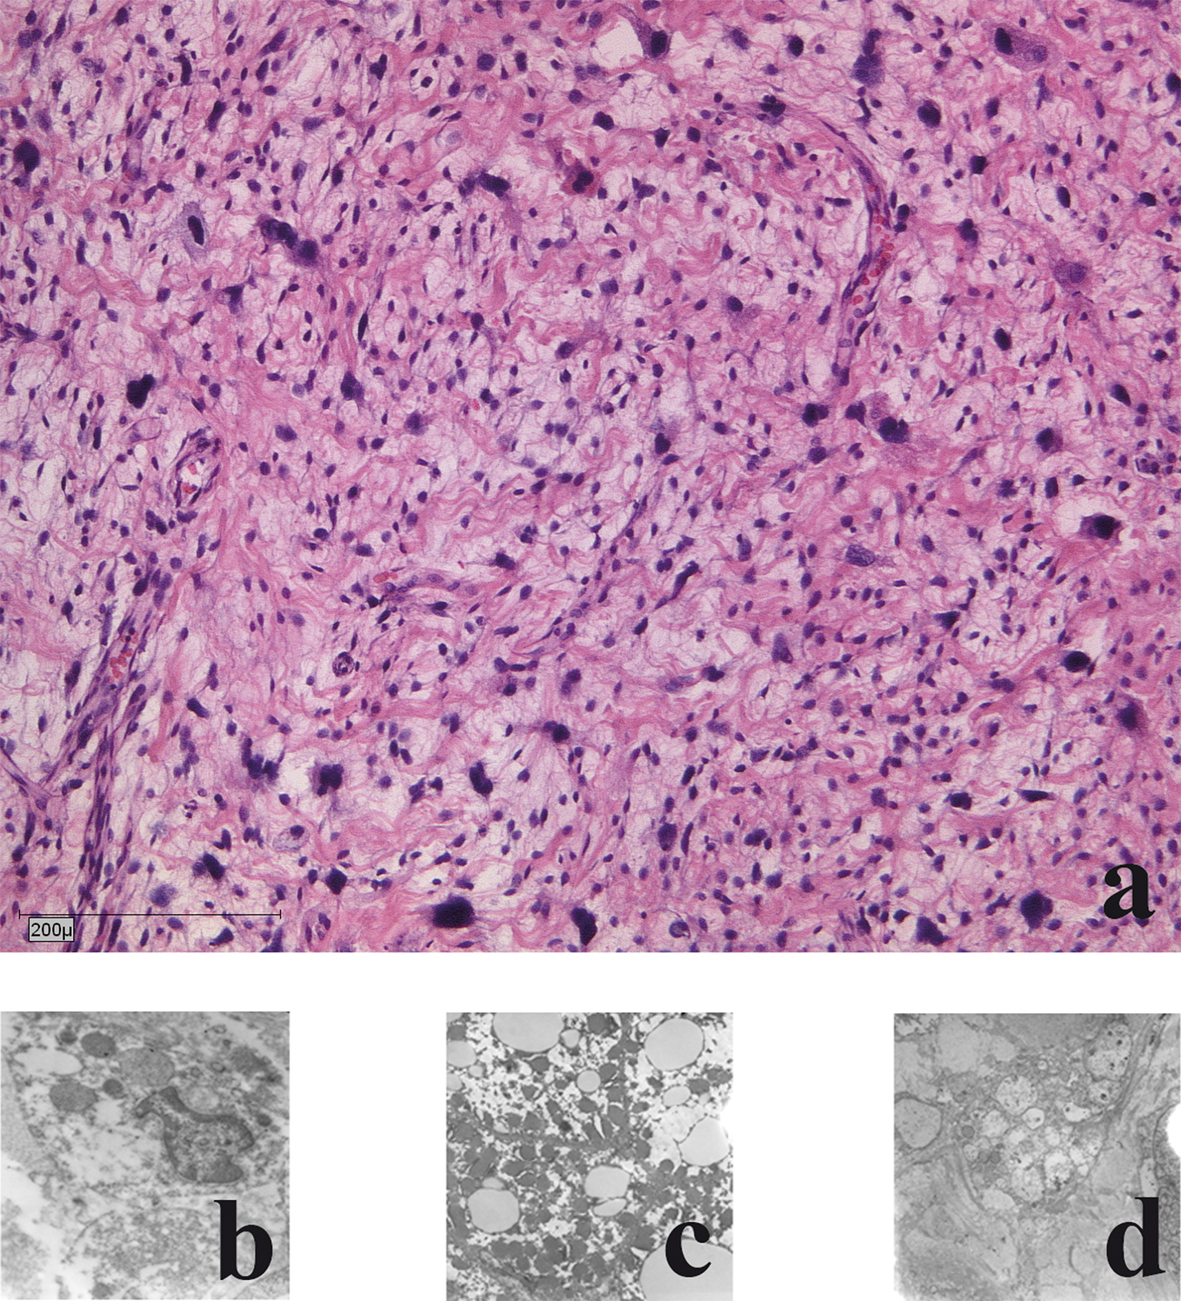

Histological and electronmicroscopic morphology of the primary tumours

The liposarcomas showed a pleomorphic growth pattern with atypical mitoses and a marked increase in nuclear and cell changes. Bizarre pleomorphic lipoblasts were seen next to spindle shaped tumour cells, even some giant cells were found. Myxoid changes were rare and tumour necrosis was seen in 15 % of areas. Pancytokeratines (MNF116), EMA, smooth muscle actin, desmin, S100 and CD34 were negative (Fig. 2a).

![]() Click for large image | Figure 2. Histological and electron-microscopic morphology of the primary tumour: a) haematoxylin and eosin staining; b) Nuclear morphology demonstrates large atypical cell nuclei with heterochromic prominent nucleoli; c) Cytoplasm: few reticular endoplasmic reticuli with few dark elongated elliptical mitochondria; d) Lipid vacuoles: few with no accumulation of glycogen. |

Electron microscopic analysis showed malignant cells with mostly decreased rough endoplasmic reticulum and heterogeneity of cells and nuclei size and shape were present. Nuclear irregularities with multiple nucleoli were frequent. Nucleoli were increased in size and number. The sarcomatous cells had highly irregular nuclear profiles. Mitochondria were electron dark and elongated. Golgi complexes were present. No accumulation of glycogen was seen. Mitotic accumulation of lipid globules was a frequent finding. Few giant cells were present. Focally necrotic areas were seen (Fig. 2b-d).